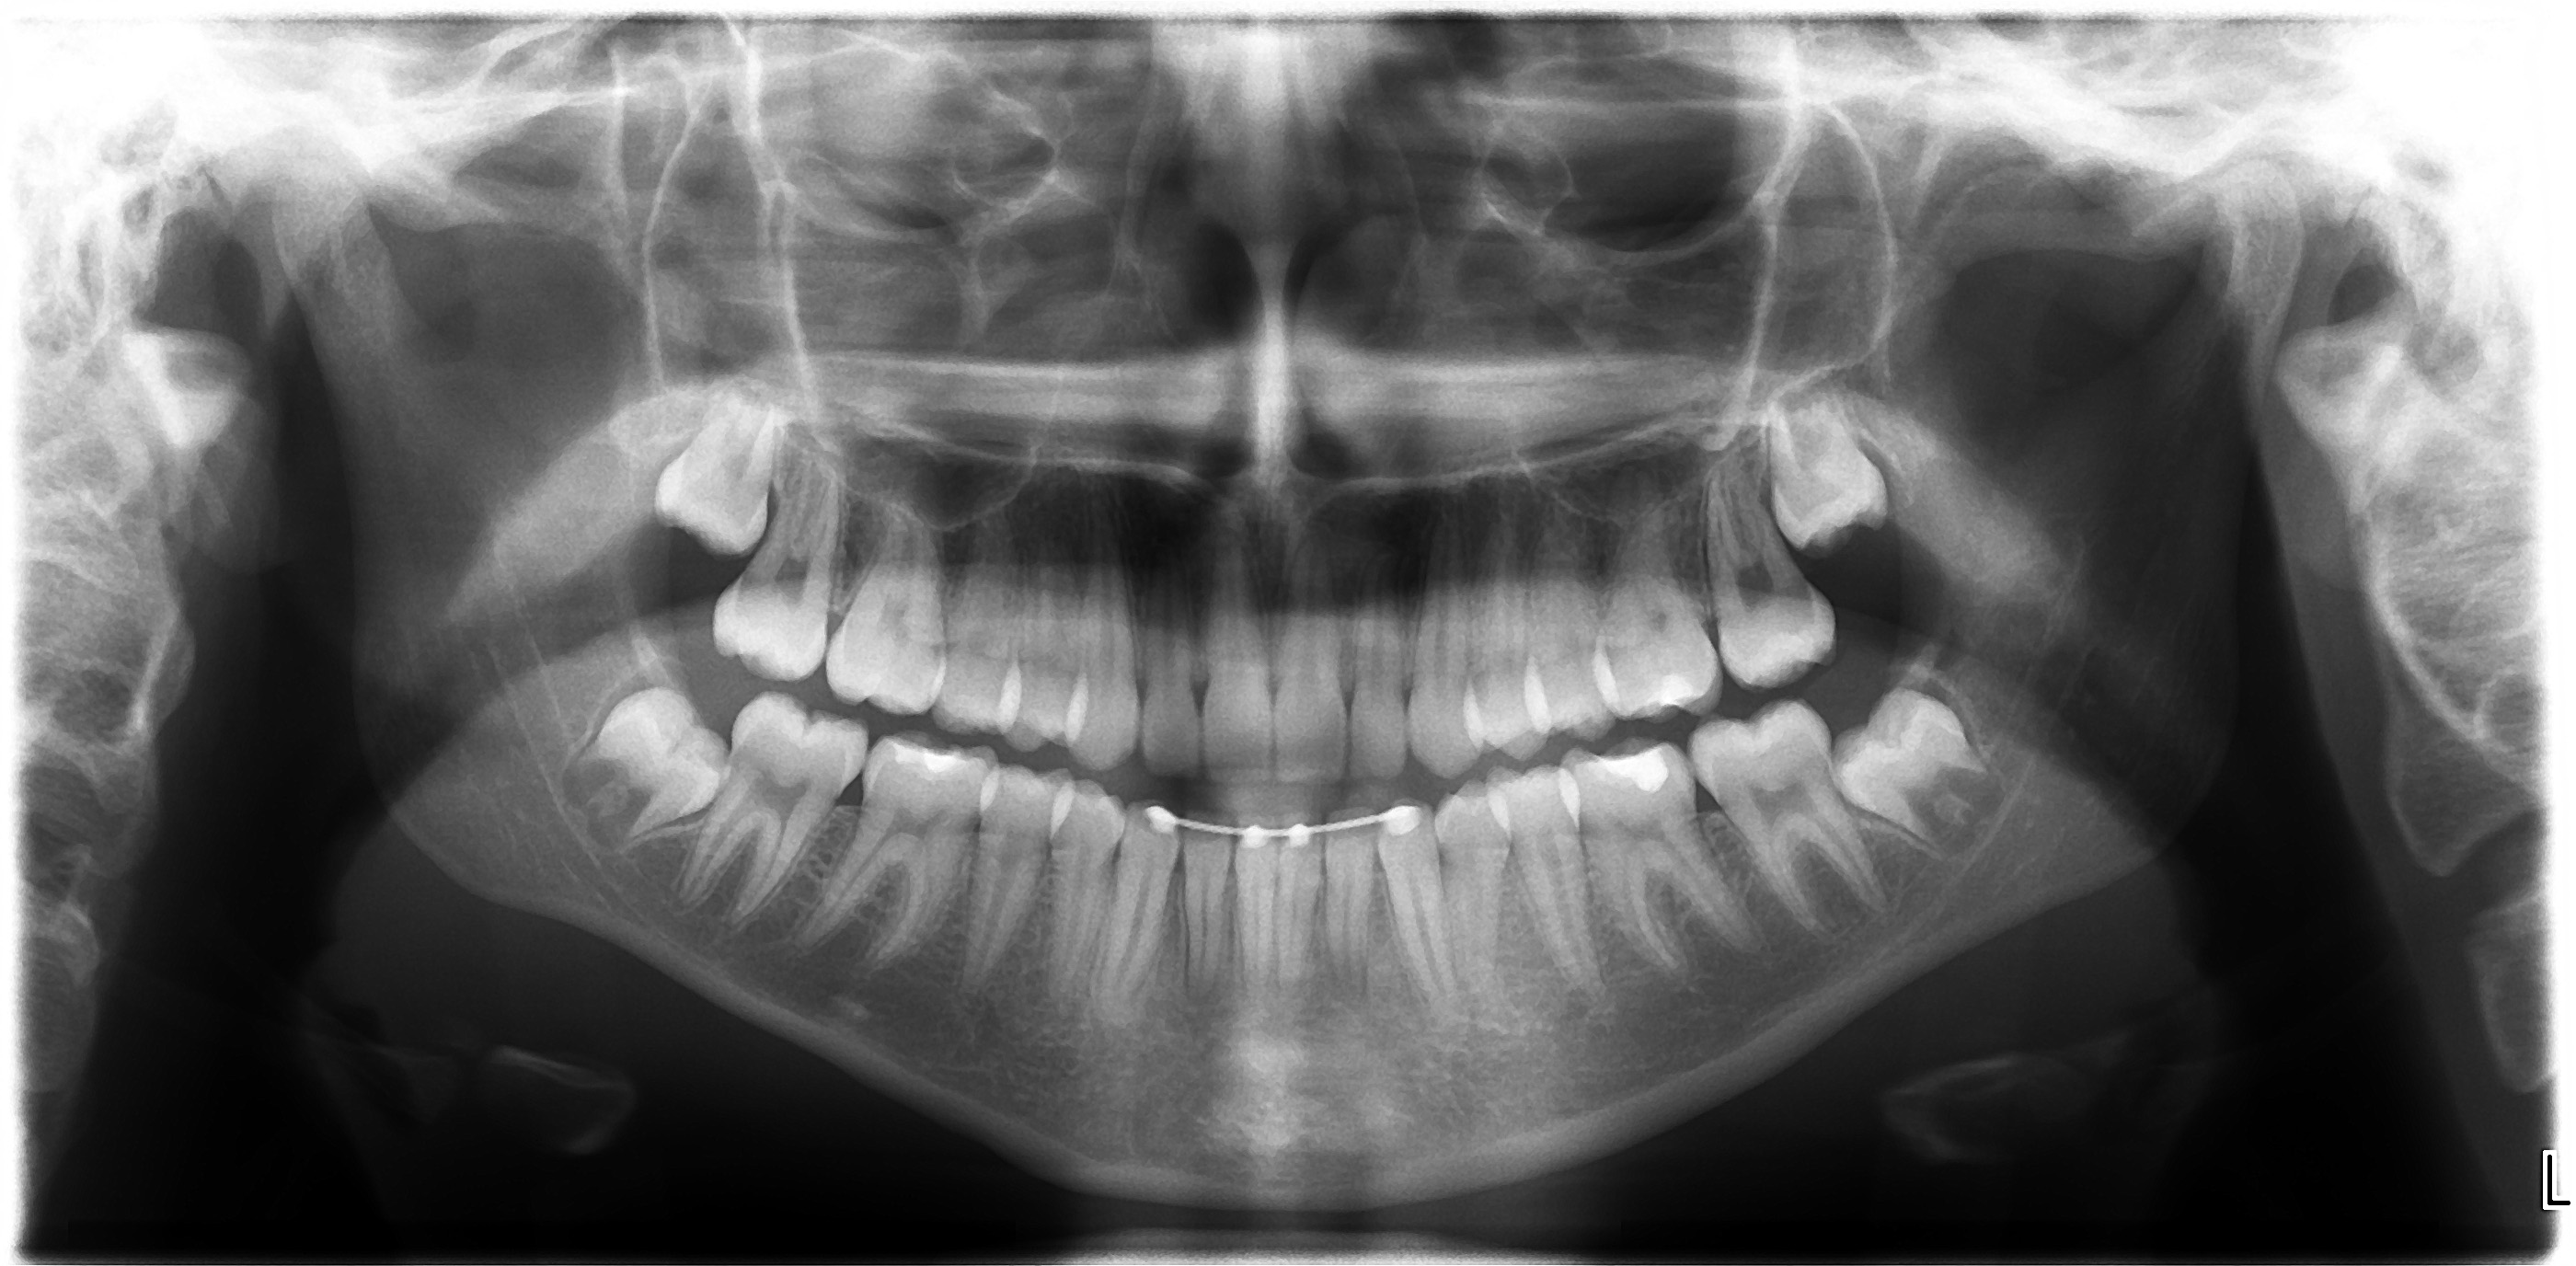

Final Results of Unilateral Class II Malocclusion

After using Rapid Molar Distalizer.  Total treatment lasts 50 months.